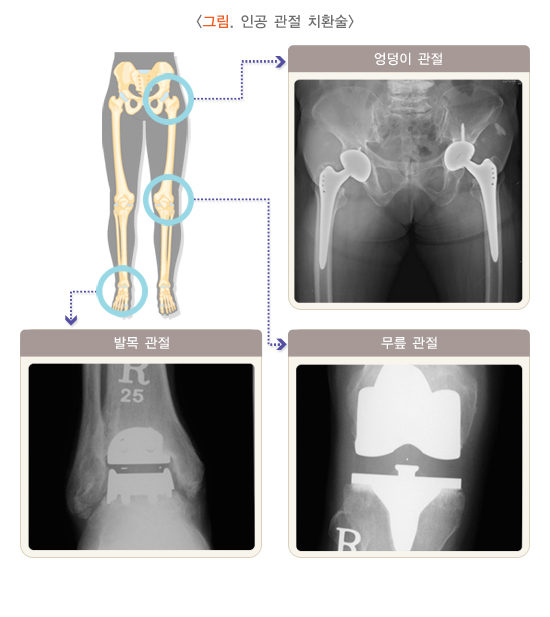

(4) 관절 성형술(치환술)

관절 성형술은 보다 심한 관절염에서 고려되는 방법으로, 인공 관절 치환술이 대표적이고 효과적인 방법입니다.

인공관절 치환술은 원래의 관절을 대치하는 방법입니다. 골관절염의 경우 비구와 대퇴골 두가 동시에 손상되어 엉덩이 관절의 전체를 바꾸어 주는 전치환술이 가장 보편적으로 이용되고 있습니다.

(5) 인공 관절 치환술

인공 관절 치환술은 한 구획 치환술과 전치환술로 나누어 볼 수 있습니다. 한 구획 치환술은 활동이 많지 않으며 한쪽 구획에만 관절염이 심하지만 90도 이상의 관절 운동이 가능하여 다리가 거의 다 펴지고, 내외반 변형이 15도 이하인 60세 이상 환자의 경우에 시행할 수 있습니다.한 구획 치환술은 수술할 때, 병변이 없는 관절 구조물을 보존함으로써 무릎 관절의 기능을 원활히 하고 위치 감각을 유지할 수 있습니다. 관절 운동 범위가 정상에 가까우며 수술 시간이 짧고 병원 재원일을 줄일 수 있는 장점이 있습니다. 한 구획 치환술은 수술 술기가 어려워 수술 성적이 좋지 않다는 문제점이 있었으나 최근 적용 범위를 엄격히 하고 인공 삽입물 및 기구의 개발과 정확한 수술 기법으로 보다 나은 결과를 보이고 있습니다.

무릎 관절 전치환술은 퇴행성 변화가 현저히 진행되고 통증의 정도가 심할 때 무릎 관절의 운동과 안정성을 유지하면서 통증을 없애는 목적으로 시행합니다. 초기에는 전치환술의 실패가 많았으나, 현재는 인공 관절 치환물의 설계가 많이 개선되어 향후에 관절 사이에 위치하는 폴리에틸렌 재질이 향상되면 더 좋은 성적을 얻을 수 있을 것으로 기대됩니다. 또, 최근에는 기술의 발전과 함께 새로운 수술법이 무릎 관절 전치환술에 도입되어 과거의 수술과는 또 다른 분야가 개척되고 있습니다. 환자의 병에 걸리는 비율을 감소시키고 조기 활동을 가능하도록 수술 절개를 작게 하는 최소 침습적 수술과 수술의 정확도를 높이기 위해 컴퓨터를 수술에 도입하는 컴퓨터 항법 인공 관절 치환술 등이 시도되고 있습니다.

발목 관절의 경우에도 보존적 요법을 먼저 시행하도록 하고, 심한 골관절염에서 과거에는 유합술이나 절골술 등이 주로 이용되어 왔습니다. 최근에는 연골 이식술이나 발달된 술기와 인공 관절 기구의 개발로 발목 관절의 전치환술이 다시 각광을 받고 있습니다.